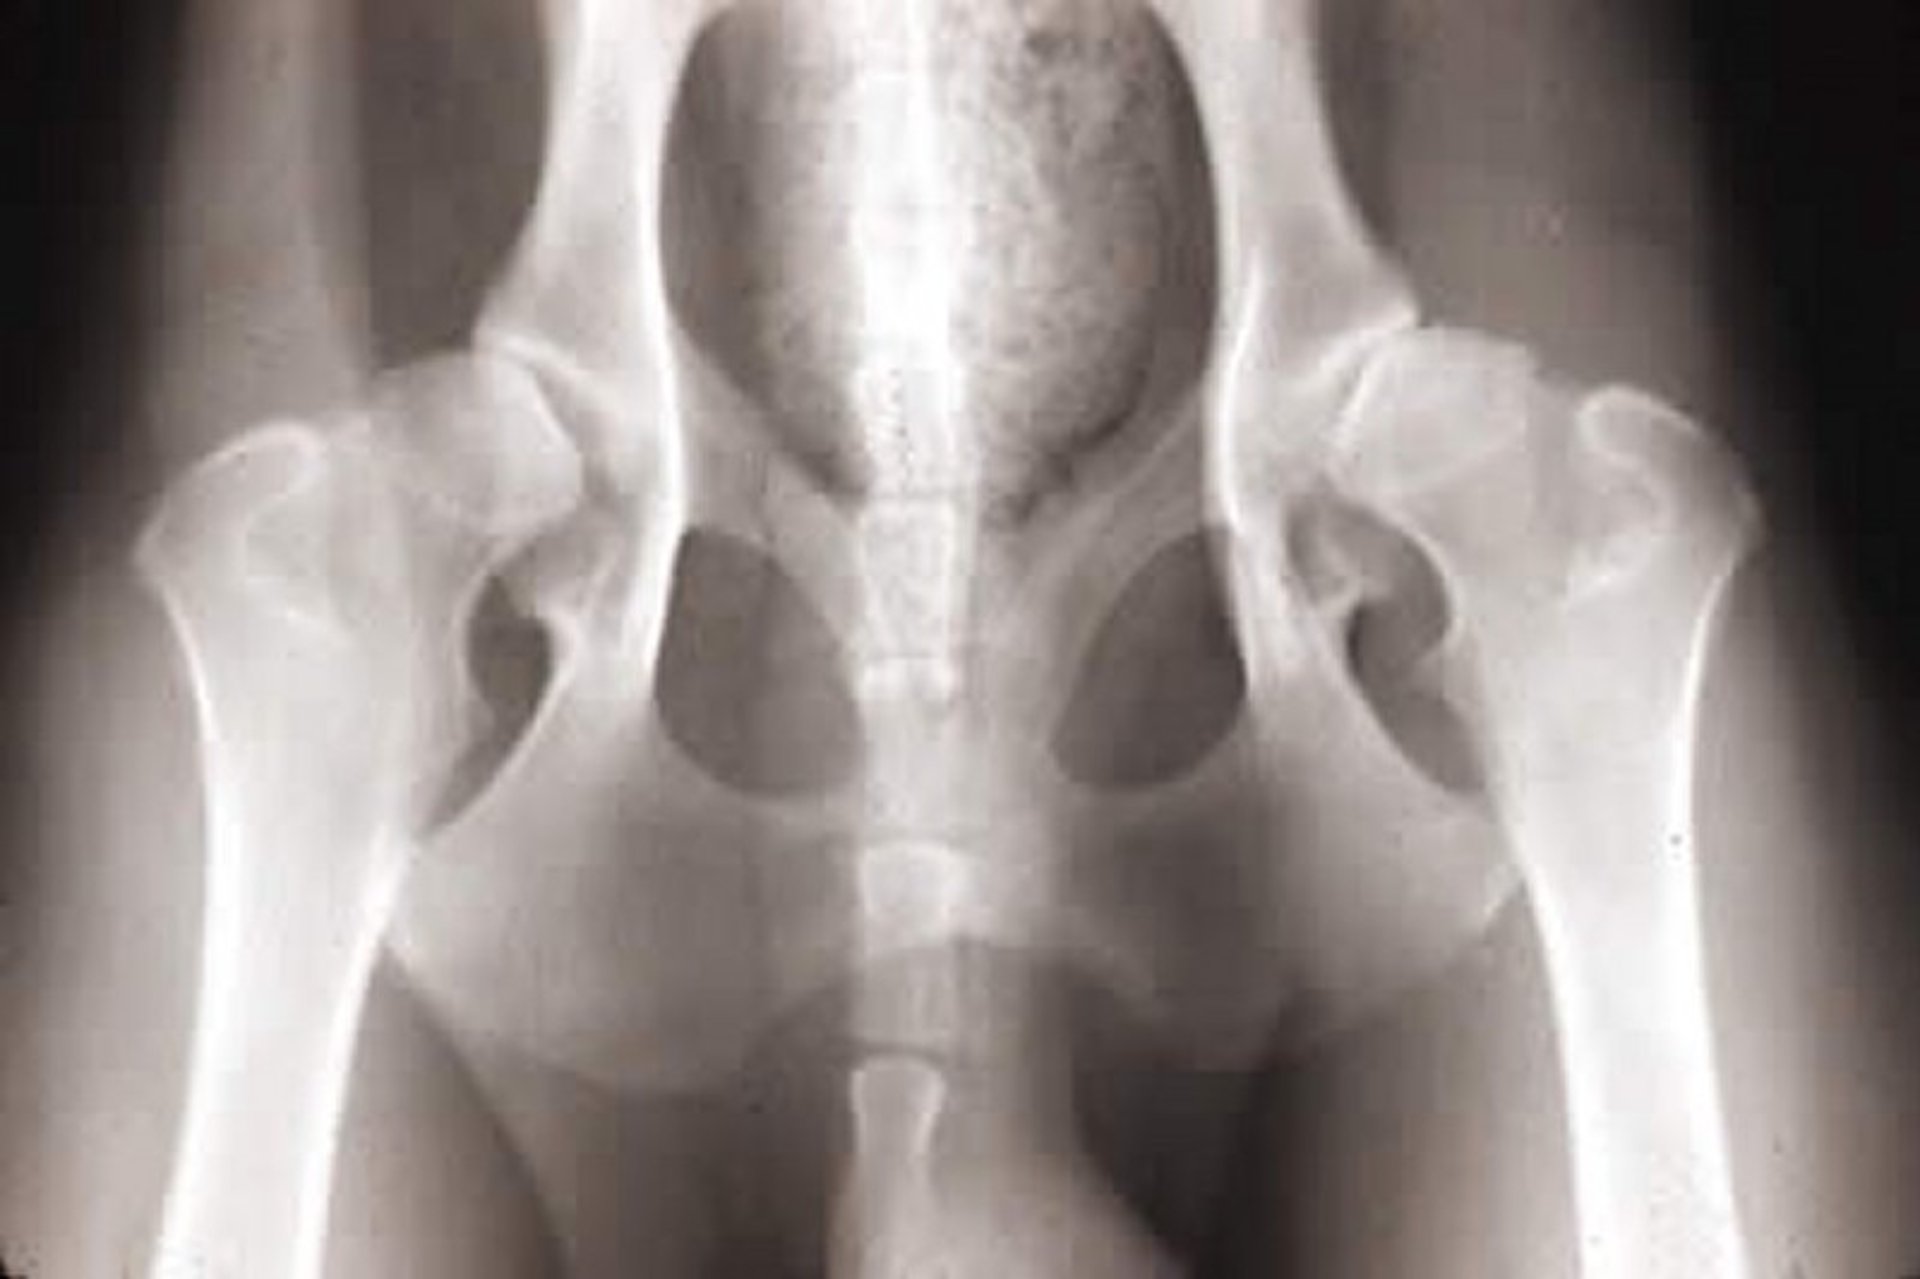

Hip dysplasia, radiograph, dog

Ventrodorsal radiographic view of the pelvis of a 2-year-old German Shepherd Dog with hip dysplasia. Note the subluxation of the hip joints, widening of both joint spaces, thickening of the femoral necks, osteophytosis, and femoral head deformation.

Courtesy of Dr. Ronald Green.